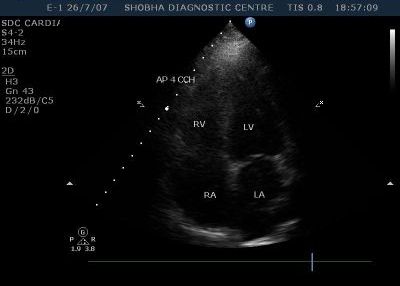

2D & Color Doppler Echo

2D Echo with Doppler is an examination that is performed on the ultrasound machine to detect abnormalities of the heart. It is used in many situations to detect cardiac function and ejection, valve motion, as a pre operative fitness test, to look for fluid around the heart, and motion abnormalities.

State of art equipment